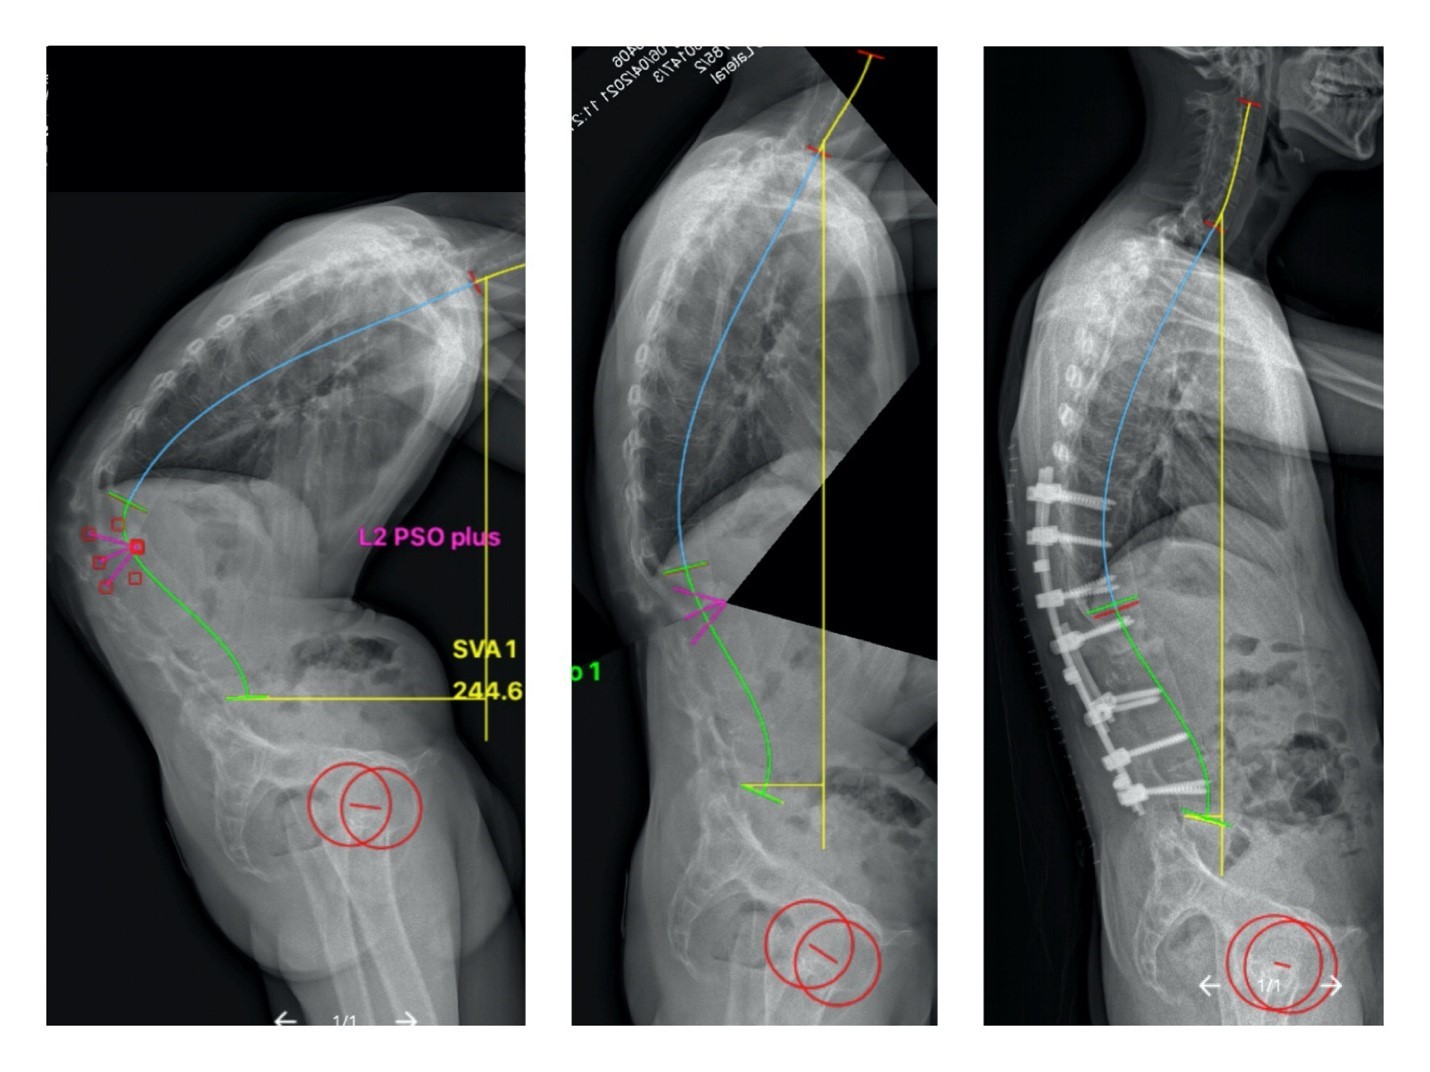

| Hình ảnh Xquang cột sống của bệnh nhân theo tiến trình nắn chỉnh. |

Để đạt hiệu quả cao nhất, các bác sĩ phải lập kế hoạch nắn chỉnh, với sự trợ giúp của phần mềm điện toán chuyên dụng. Khi đó, sẽ giúp xác định vị trí và mức độ đục xương tối ưu, dự đoán hình dáng cột sống sau phẫu thuật. Phẫu thuật viên có thể điều chỉnh chiến lược nắn chỉnh phù hợp.

Hình ảnh X-quang sau phẫu thuật cho thấy bác sĩ đã chỉnh được hơn 60 độ góc còng ban đầu. Nhờ đó, phục hồi lại dáng đứng thẳng cho bệnh nhân